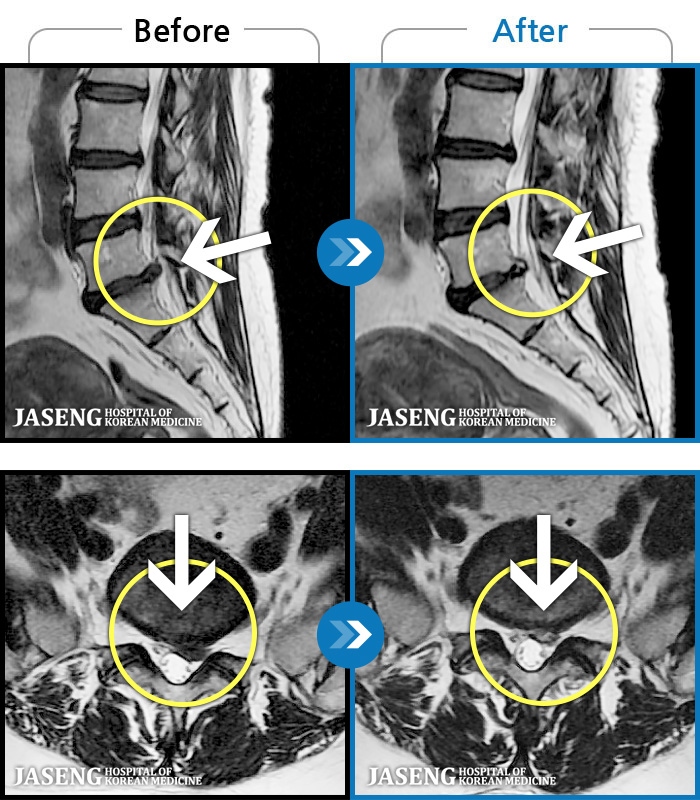

65 MRI ũ ʸ Ȯϼ.